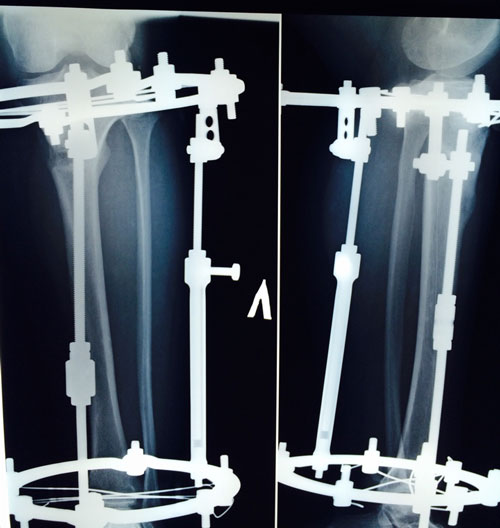

Ножки супер! разрешено всё без ограничений, все нагрузки: спорт, фитнес, каблуки любых размеров - Вам очень они пойдут! Нельзя: беременеть в течении первых 6 месяцев с момента снятия аппаратов!

Не забывайте про наш форум, высылайте фото ножек, пишите отзывы, нам это важно, это наша работа - искусство, которым мы гордимся!